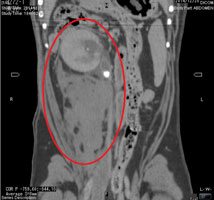

結石破砕治療の実際 – Radiology@Home。尿路結石の治療について | 医療法人社団實理会 東京国際大堀病院。尿路結石外来|尼崎市 おかだ腎泌尿器・ペインクリニック| 阪神。ぷっち おまとめ2袋 白米10キロ。尿路結石症(腎結石・尿管結石)の治療法 - 船橋クリニック 千葉。体外衝撃波結石破砕装置(ESWL)|焼津市立総合病院。尿路結石の検査 - 船橋クリニック 千葉県泌尿器科 尿路結石症。痛みを乗り越えた者だけが手にする秘宝商品説明これは単なる石ではありません。長きにわたり忍耐と痛みを経験した末、身体から生まれた奇跡の結晶です。賢者の石と呼ばれるにふさわしい、神秘的な輝きを放つ逸品!その力強い存在感は、あなたのコレクションに一層の深みを与えることでしょう。おすすめポイント•世界に一つだけのオリジナル品!•痛みを耐え抜いた歴史を感じられるストーリー付き•お守りやアクセサリーの材料にも最適こんな方におすすめ!•面白グッズ好きな方•他人とは違うコレクションを目指す方•人生の痛みを乗り越える象徴が欲しい方これを手にすることで、あなたも「賢者」の仲間入りを果たせるかも?一点限りの出品ですので、お見逃しなく!。尿管結石の最新治療技術 - Genspark。尿路結石症 – 社会医療法人 北腎会 坂泌尿器科千歳クリニック。尿管結石の最新治療技術 - Genspark。巨大腎結石への挑戦 | 研究報告 | 医療法人社団實理会 東京国際。尿路結石(尿管結石、腎臓結石、膀胱結石)の原因や治療について。尿路結石」について|市立貝塚病院